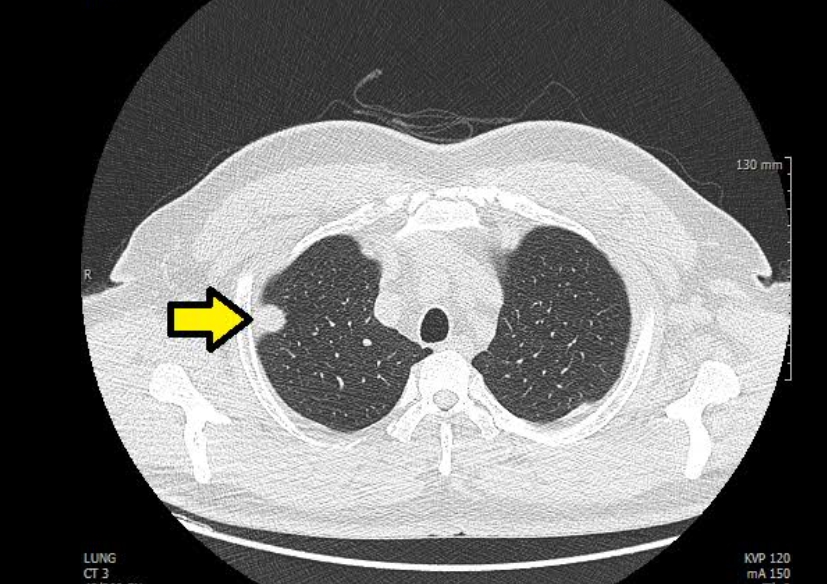

흉부 엑스레이 폐렴

폐렴은 엑스레이에서 가장 자주 발견되는 질환 중 하나예요. 정상적인 폐는 까맣게 보이지만, 염증이 생기면 하얗게 변합니다. 의사들은 이를 보고 ‘침윤(염증이 번진 상태)’이라고 표현해요.

흉부 엑스레이로 알수있는것 폐렴의 종류에 따라 모양도 달라요. 한쪽 폐 전체가 하얗게 보이면 ‘엽성 폐렴’, 군데군데 얼룩처럼 보이면 ‘기관지 폐렴’일 수 있어요. 예전에 제 친구가 독감 후 기침이 너무 오래가서 병원에 갔는데, 엑스레이에 하얀 구름처럼 음영이 보여 폐렴 진단을 받았죠. 약을 꾸준히 먹고 다시 찍었을 땐 그 구름이 걷힌 것처럼 깨끗했어요. 이렇게 눈에 보이는 회복의 흔적이 참 다행스럽습니다.